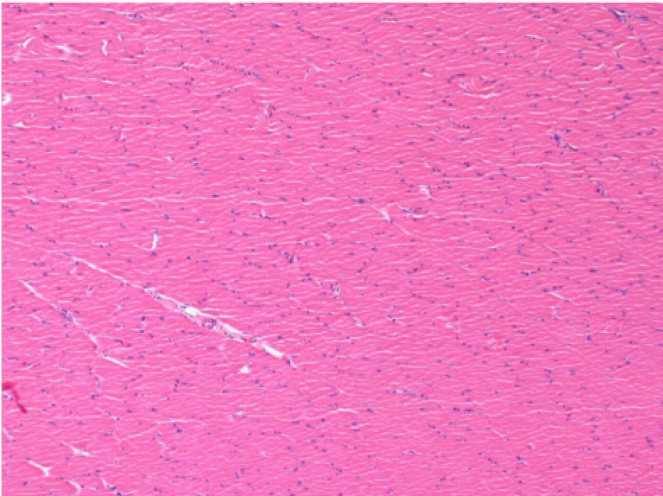

7 months after Endopeel Injection

7 months (D210)after Endopeel IM Injection 0.1ml in the right pretibial muscle.

Complete Restitutio ad integrum after 7 months

L : Control-100xD210

R:100xD210

L :Control 50xD210

R50X-D210